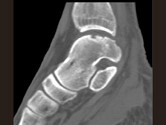

- 单项选择题男,17岁, 踝关节疼痛,关节作响, 结合图像,最可能的诊断是 ( )

B、剥脱性骨软骨炎